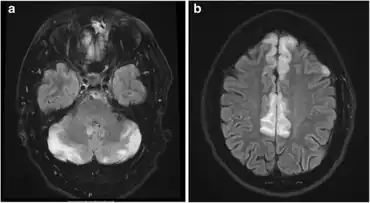

Cerebral edema can be generalized or focal. Brain ventricles are compressed, cortical gyri flattened.

Diagnostic methods for hypertensive encephalopathy include physical examination, blood pressure measurement, blood sampling, ECG, EEG, chest X-ray, urinalysis, arterial blood gas analysis, and imaging of the head (CAT scan and/or MRI). Since decreasing the blood pressure is essential, anti-hypertensive medication is administered without awaiting the results of the laboratory tests. Electroencephalographic examination detects the absence of alpha waves, signifying impaired consciousness. In people with visual disturbances, slow waves are detected in the occipital areas.